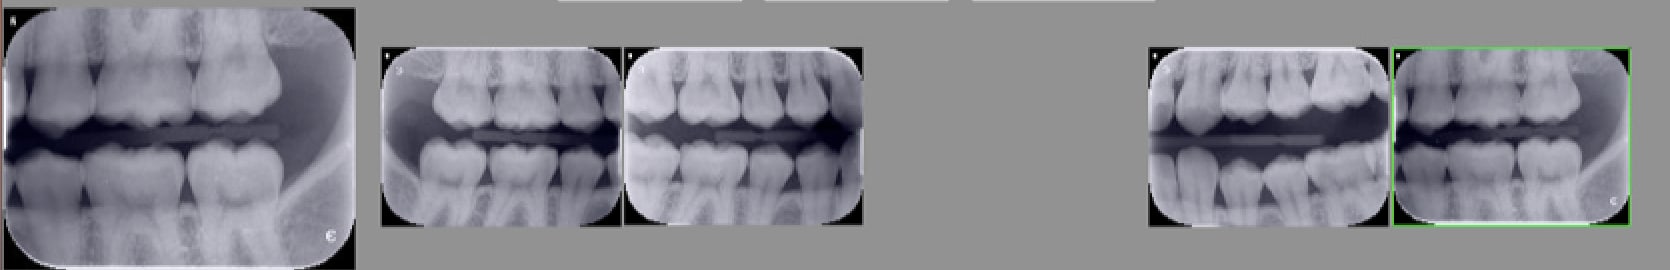

> En pratique, avec un capteur taille 2 je vois les 7-6-5 et 4 sur un seul cliché.

> Et je ne me risque pas à facturer 4 secteurs par cliché ! Donc 1 cliché à gauche

> et un à droite.

Oui donc tu t’arranges pour en faire 4 .

Un pour 7-6-5 un autre pour avoir la 4-3 . Et idem de l’autre coté . C’est pas con . Faut bien viser profond pour ne pas avoir les 4 sur le premier cliché.